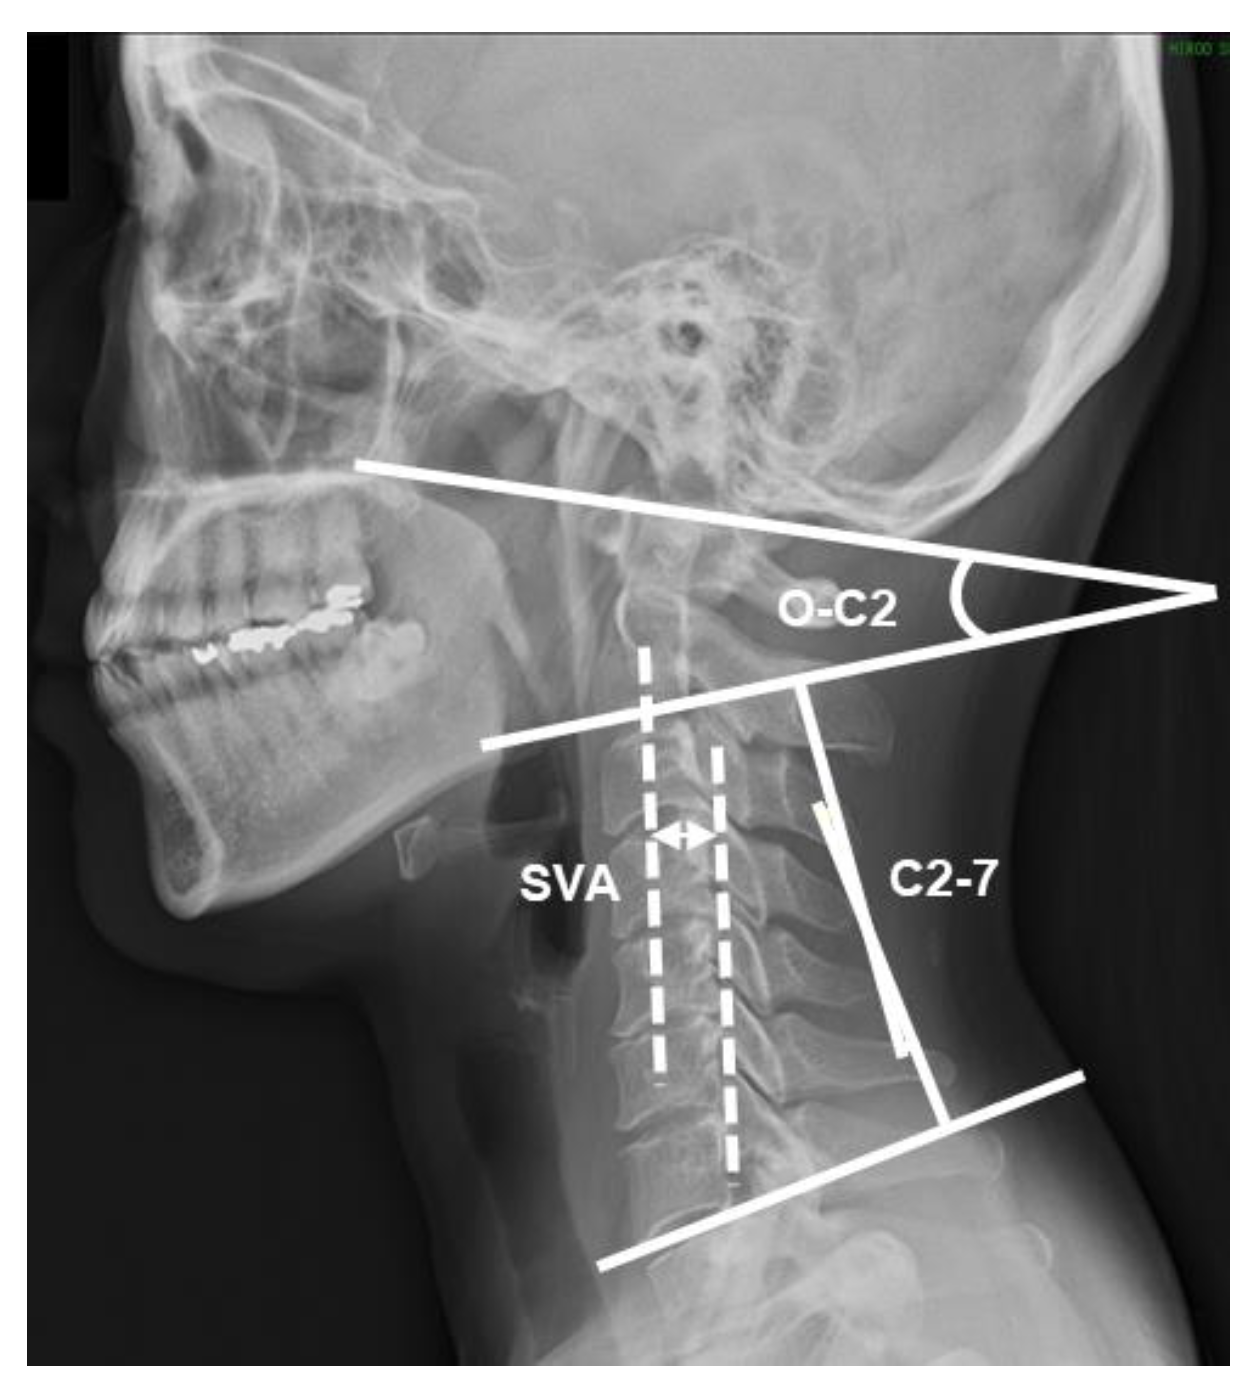

2.3. Radiographic Measurements